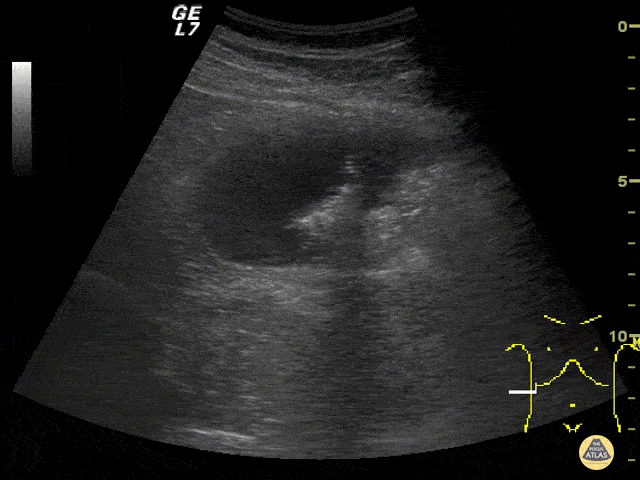

This is an image from a 55 years gentleman with suspected biliary colic. A gallstone was confirmed however the patient's symptoms during exam did not match classic biliary colic. A more in depth evaluation of the right upper quadrant confirmed the presence of a right colonic mass. Color flow was appreciated on a separate clip. Although bowel pathologies are an uncommon finding with emergency ultrasound, they can be easily found with further investigation in atypical presentations. Stefanie Tamburrini, MD Emergency Radiologist